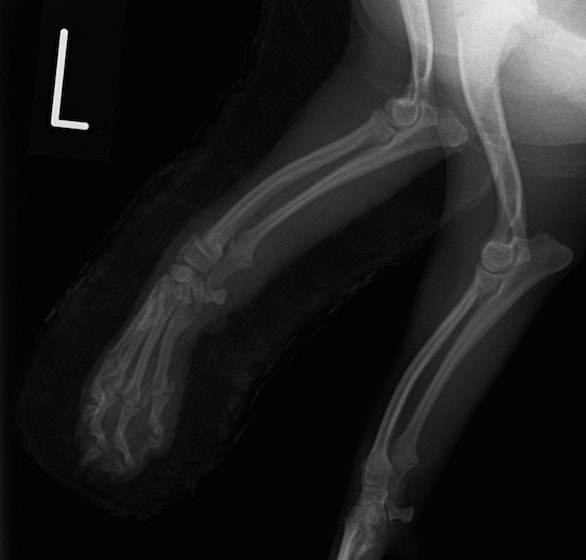

ペルシャ猫 11ヶ月齢 雄

他院にて左大腿骨遠位の成長板骨折(salter-harrisⅠ型)が認められており、治療相談を目的として来院。当院にて、キルシュナーワイヤーを用いたピンニングにより骨折部位の整復を行いました。術後の経過は良好で、現在も経過観察中です。

術前レントゲン

術後レントゲン